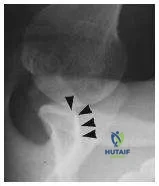

A glenoid profile radiograph (Slide) of a 21-year-old male rugby player with multiple traumatic anterior shoulder dislocations is presented. Which of the following is the preferred treatment:

Orthopedic Prometric Exam Chapter 3 Image

Explanation

The radiograph demonstrates anterior glenoid rim insufficiency, which is a risk factor for failure of soft tissue reconstructions especially in contact athletes. The arrows on the figure represent the anterior border of the glenoid rim. A coracoid transfer procedure to reconstruct the anterior bony deficiency maximizes the possibility for successful restoration of shoulder stability.